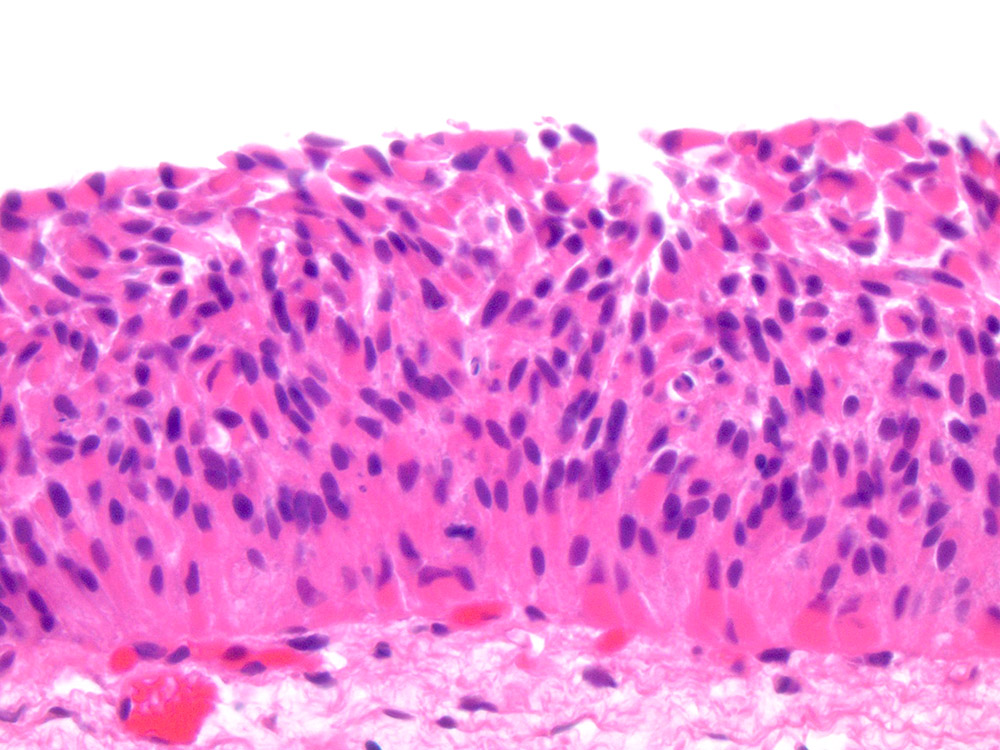

Consensus grade: Atypia/dysplasia

Case description (by case creator):

Flat lesion